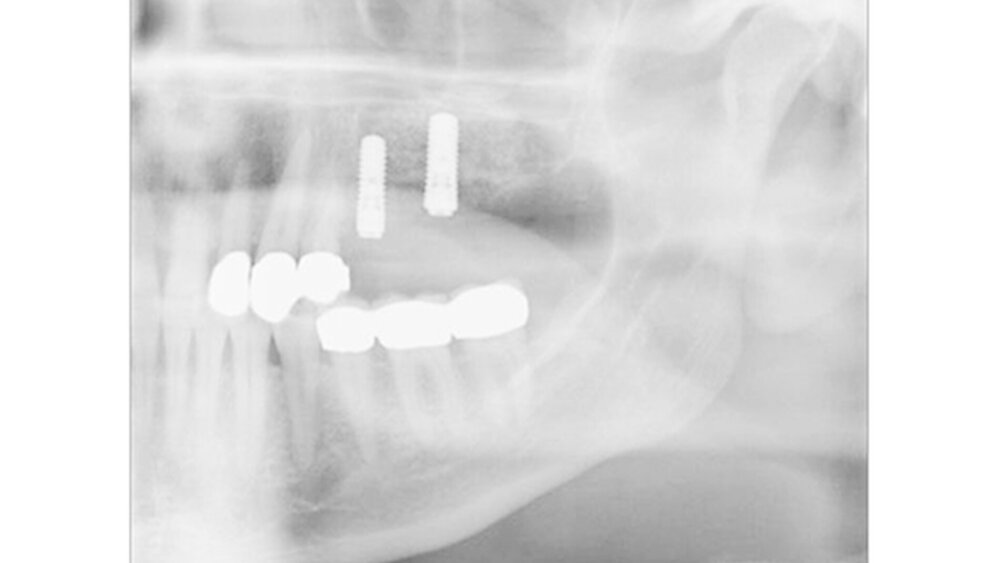

Patienten mit schlecht eingestelltem Diabetes mellitus scheinen eine verzögerte Osseointegration nach der Implantation aufzuweisen. Nach einem Jahr scheint es jedoch keinen Unterschied in der Implantatstabilität zwischen Diabetikern und gesunden Personen zu geben, auch nicht bei schlecht eingestelltem HbA1c.

Die Überlebensraten von Implantaten zeigen bei Diabetikern in Studien von bis zu sechs Jahren keine signifikanten Unterschiede zu Nicht-Diabetikern, in einem Beobachtungszeitraum bis zu 20 Jahren ist eine reduzierte Implantat-Überlebensrate bei Diabetikern erkennbar.

Aufgrund von Hinweisen auf eine verzögerte Osseointegration sollte die Indikation für eine Sofort- und Frühbelastung kritisch gestellt werden.